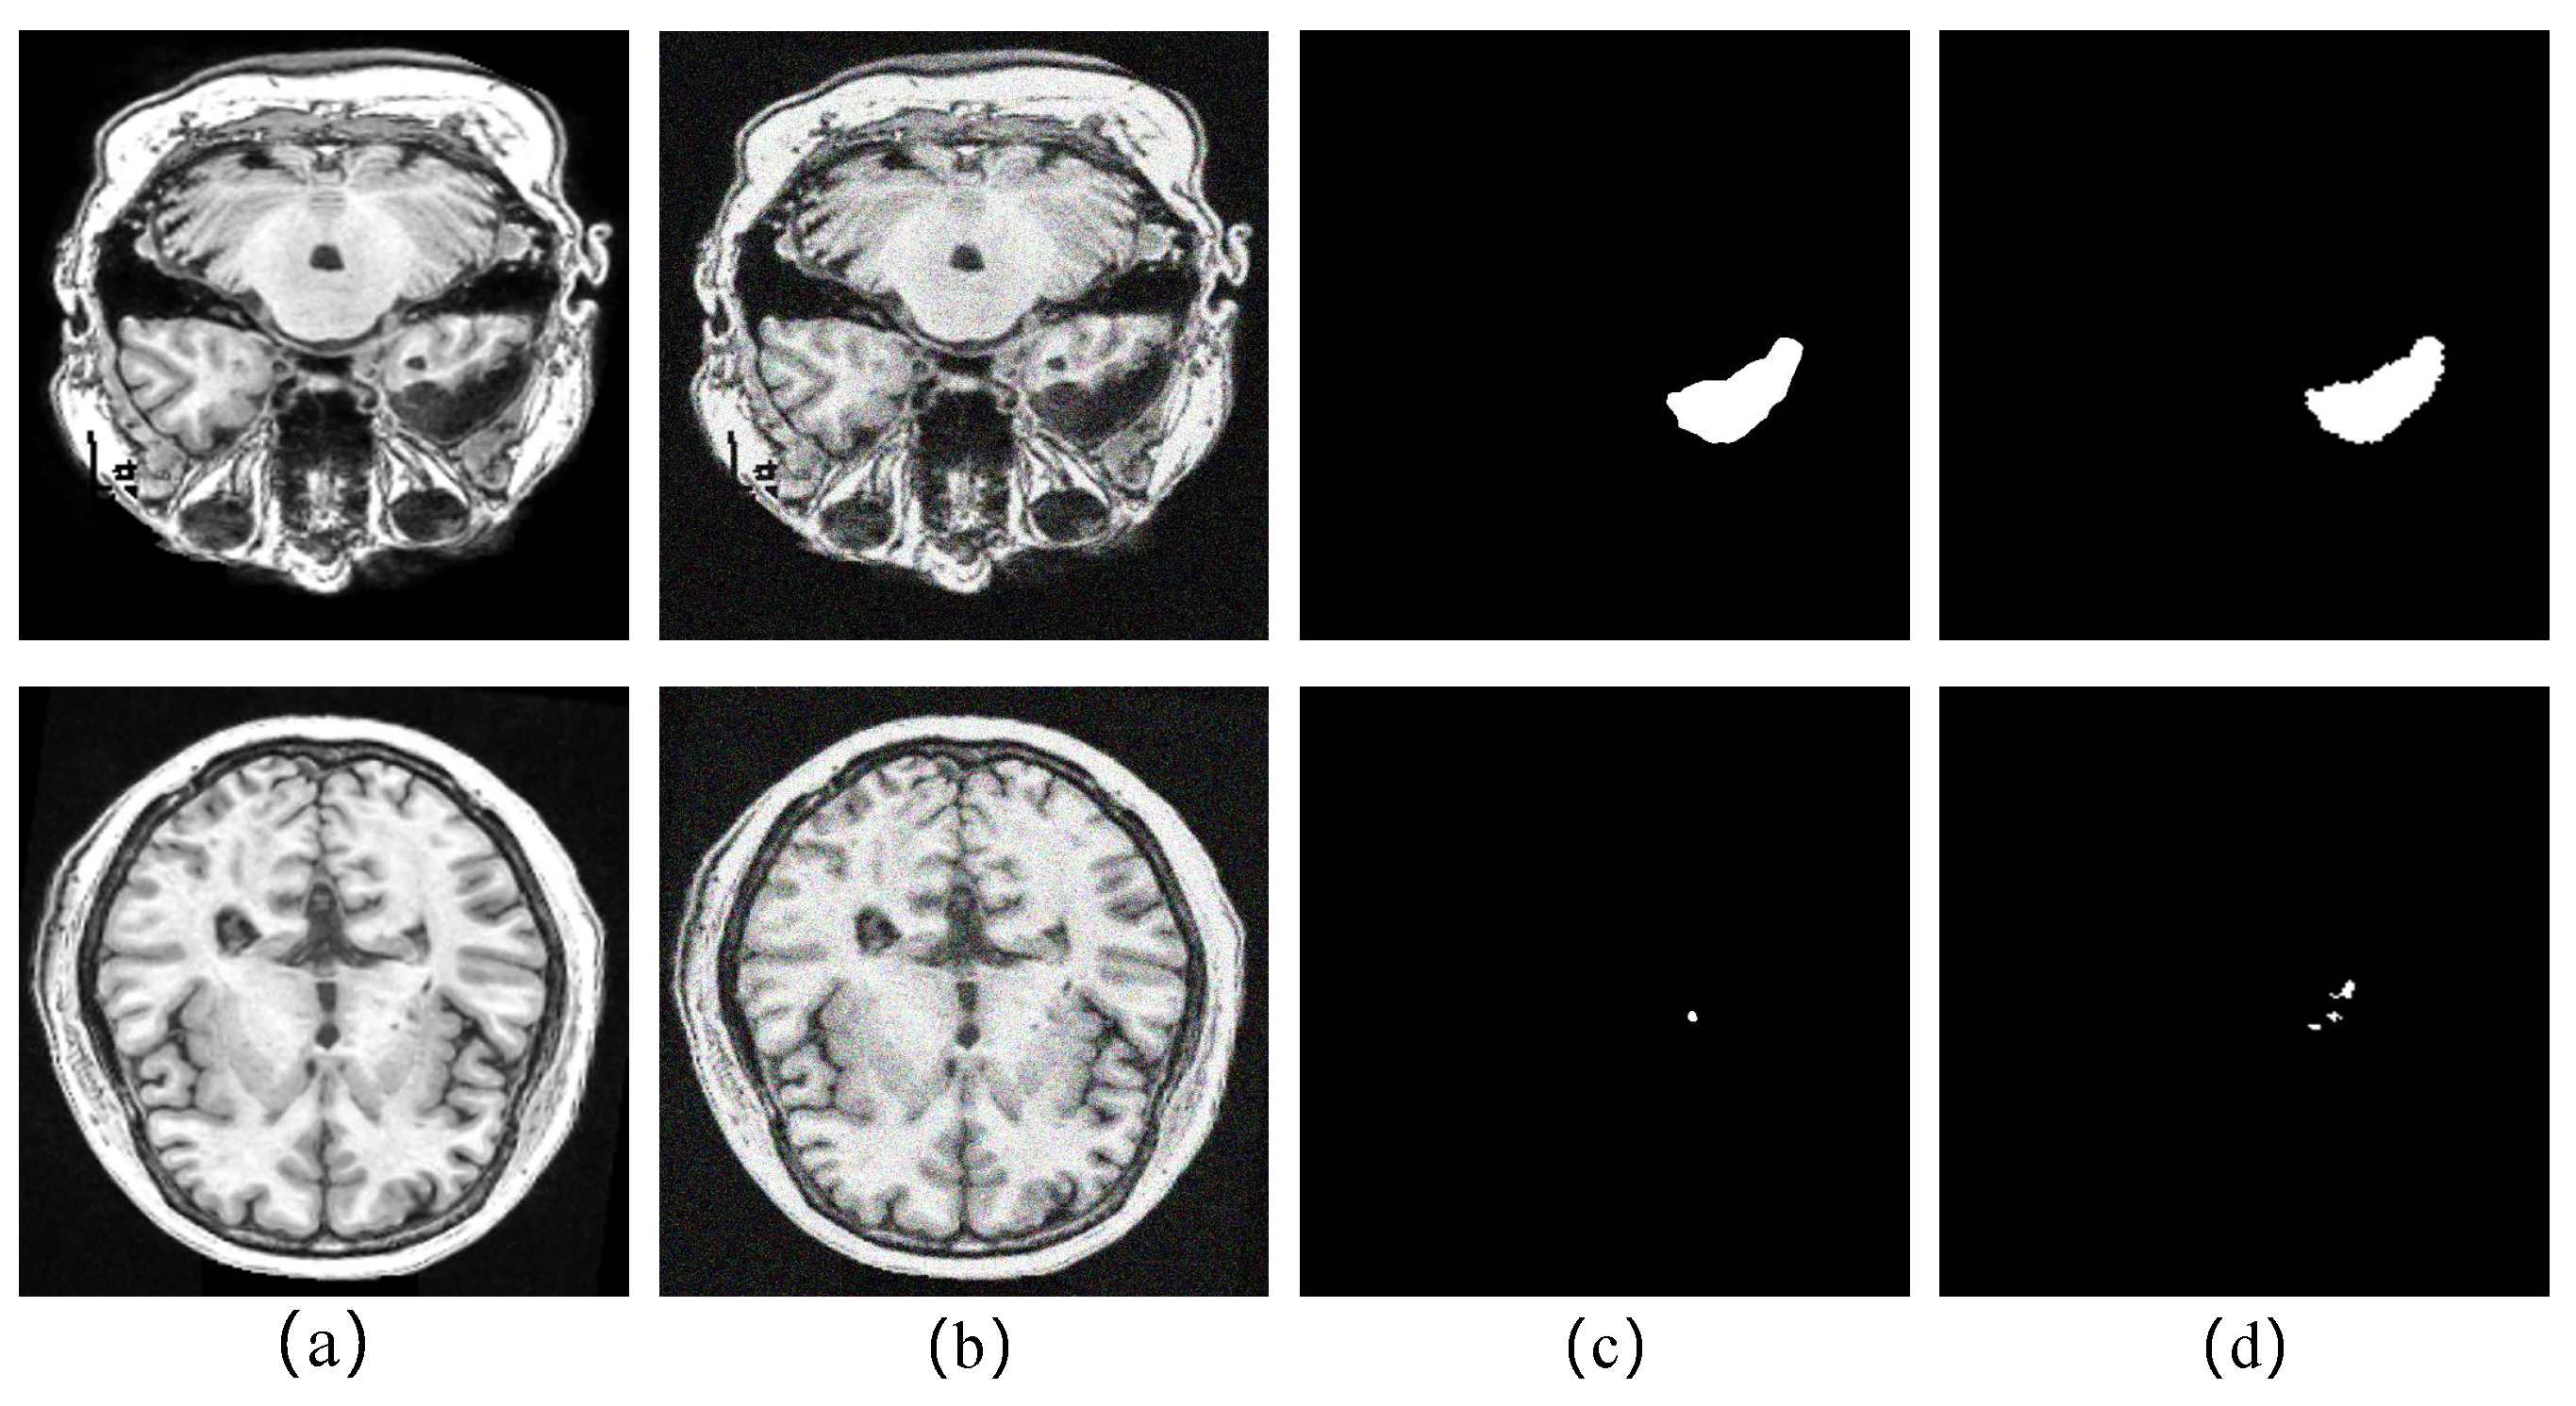

5.4. Analyze the Robustness of the Proposed Method to Noise

The noise in real-world biomedical images is a well-known problem that reduces the accuracy of diagnostics. In order to verify the robustness of our proposed model to noise, we processed images of large, medium, and small tasks with Gaussian noise, and we set the σ of Gaussian noise to 40 to make the noised image more realistic. Table 7 shows the performance changes of the model in the main indicator DSC before and after adding noise. We can observe that the segmentation performance of each task drops after noise addition, especially the small object task, which drops by 23.25%. This is because, after noise enhancement, the context information of each pixel is mixed with noise information, leading to deviations in the high-level semantic information encoded by the model. Context information plays an important role in small target localization tasks. As shown in Figure 7, the model is prone to the problem of missing localization in noisy small target tasks, but it is undeniable that FECC-Net still shows excellent performance in the task of dealing with noisy large objects; this is because the squeeze-and-excitation blocks in the encoder play a role in suppressing the noise.

Figure 7. Qualitative analysis of the degradation of the model’s performance after adding noise: (a) original image; (b) Gaussian noise-processed image; (c) segmentation result of noisy image; (d) ground truth.